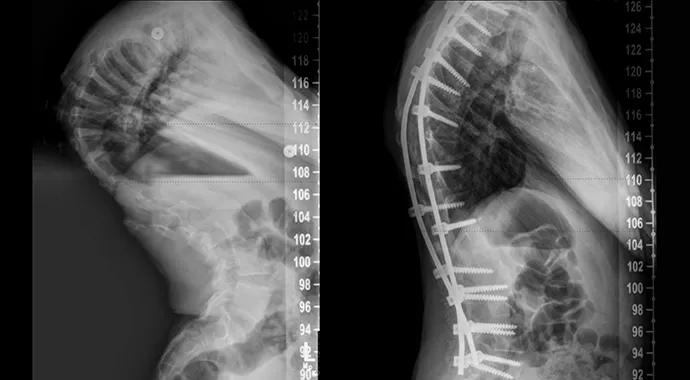

Radiographs revealed a 90-degree thoracic curve, a 67-degree lumbar curve and 100-degree kyphosis. After assessment by neurology, genetics, orthopaedics, pulmonary medicine and cardiology, the patient was found to have multiple medical problems and severely compromised pulmonary function. His condition was consistent with the kyphoscoliotic form of Ehlers-Danlos syndrome.

When the patient was last seen, he had a 32-degree thoracic curve, a 27-degree lumbar curve and 51-degree kyphosis. His pulmonary function had increased by 33 percent from his initial presentation approximately six months earlier. He was ambulating with a nonantalgic gait and had gained several inches in height. His parents felt he was dramatically better not just physically (see photos below) but also psychologically and socially.

Radiographs and photographs of the case patient at presentation (left) and after spinal fusion and rehabilitation (right).